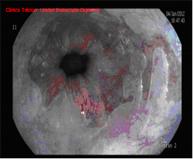

El diagnóstico se lleva a cabo mediante endoscopios de alta resolución con magnificación (aumento de la imagen), utilizando técnicas de cromoendoscopia añadidas, realizadas por endoscopistas especialistas en el diagnóstico precoz de lesiones precancerosas y la realización de biopsias que son analizadas.

Radiofrecuencia con sistema HALO

El sistema Halo de radiofrecuencia es un aparato que permite la ablación de la mucosa esofágica hasta una profundidad de 1 mm de forma segura y uniforme. La ablación es una técnica en la que se calienta el tejido hasta que deja de ser viable o estar vivo. La tecnología HALO es un tipo muy específico de ablación en la que la energía calorífica se aplica de forma precisa y controlada. Los ensayos clínicos han demostrado que el tejido de Barrett se puede eliminar completamente con la tecnología de ablación HALO en el 98,4% de los pacientes.